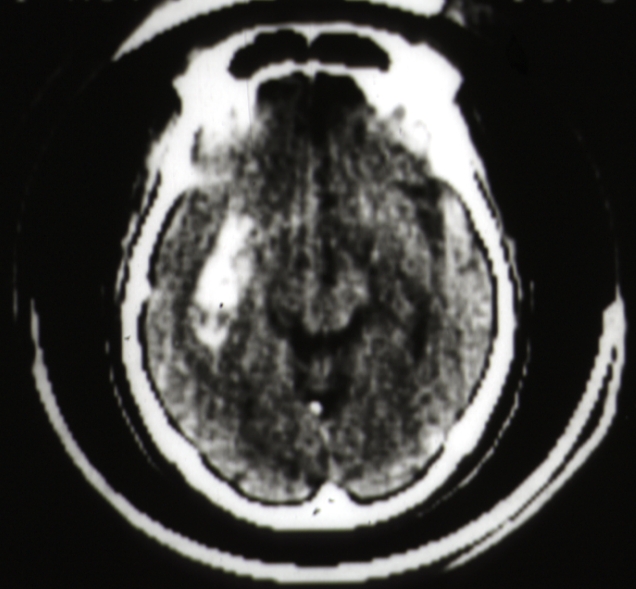

RADIOLOGY: NERVOUS: Brain: Hemorrhage: CAT scan putamen hemorrhage